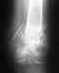

Прошу помощи по расшифровке рентгена кисти, тк ставят разные диагнозы.

ЗДРАВСТВУЙТЕ!Женщина 62 года, упала, как результат, травма кисти.Кроме этого страдает артритом?/артрозом коленных суставов и возможно артритом?/артрозом? лучезапясных суставов. Помогите, пожалуйста, определить - есть ли переломы и в каких местах?Заранее благодарю.

• Кликните для загрузки файла 16февраля 2019 2.jpg